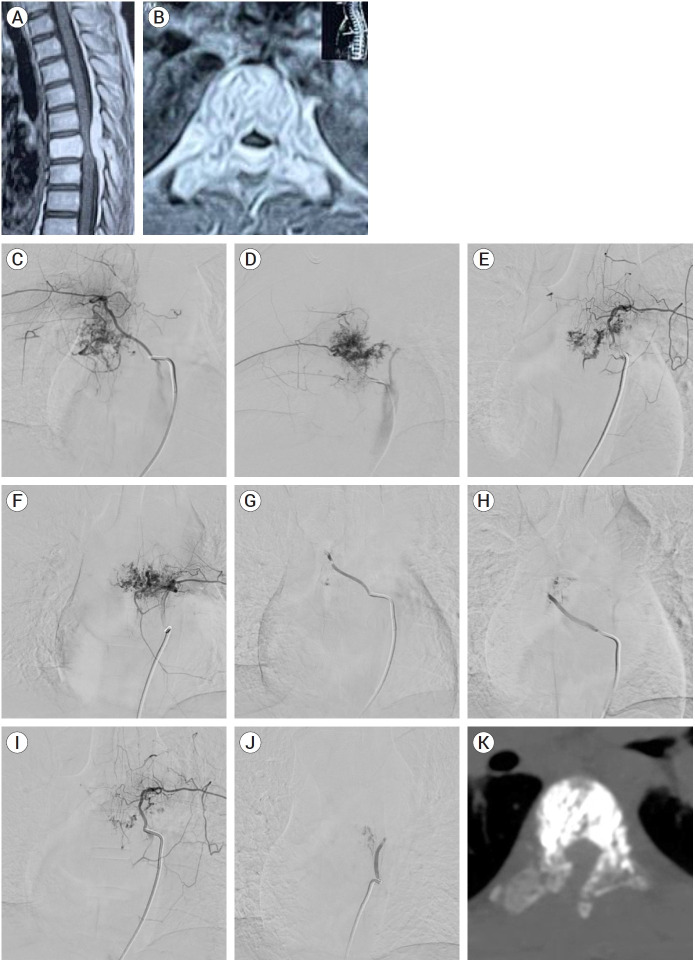

{"title":"Multi-modal management of aggressive vertebral hemangioma: A single center experience.","authors":"Mohamed Farouk, Mohamed Ali Kassem, Ashraf Ezzeldein, Mohamed Mohsen Ameen, Ali Hassan Elmokadem, Mohamed M Elsherbini","doi":"10.7461/jcen.2025.E2024.12.003","DOIUrl":null,"url":null,"abstract":"<p><strong>Objective: </strong>This study aims at spotlighting different lines of management of aggressive vertebral hemangioma (VH) through a retrospective analysis of single center experience.</p><p><strong>Methods: </strong>Patients diagnosed with aggressive VHs in a tertiary referral center were reviewed from 2014 through 2024. Data of patients who met the inclusion criteria were analyzed. Patients of all ages, both sexes, and all varieties of clinical presentation were included, only patients who underwent at least one intervention were included.</p><p><strong>Results: </strong>The study included nine patients, comprising six females and three males, with a mean age of 29.3 years (ranging from 14 to 46). Six patients underwent Trans-arterial embolization (TAE), of whom five underwent further surgical procedures, while one patient found TAE to be sufficient as a stand-alone management technique. Eight patients underwent surgical management, five of whom were pre-operatively embolized.</p><p><strong>Conclusions: </strong>Aggressive VHs are rare, and their management is challenging. Most cases require a multi-modal management, especially when presented with neurological deficit. Pre-operative embolization and/or vertebroplasty are safe and useful tools to decrease intra-operative bleeding of such a vascular pathology in cases undergoing open surgical procedures.</p>","PeriodicalId":94072,"journal":{"name":"Journal of cerebrovascular and endovascular neurosurgery","volume":" ","pages":"40-49"},"PeriodicalIF":0.0000,"publicationDate":"2025-03-01","publicationTypes":"Journal Article","fieldsOfStudy":null,"isOpenAccess":false,"openAccessPdf":"https://www.ncbi.nlm.nih.gov/pmc/articles/PMC11984272/pdf/","citationCount":"0","resultStr":null,"platform":"Semanticscholar","paperid":null,"PeriodicalName":"Journal of cerebrovascular and endovascular neurosurgery","FirstCategoryId":"1085","ListUrlMain":"https://doi.org/10.7461/jcen.2025.E2024.12.003","RegionNum":0,"RegionCategory":null,"ArticlePicture":[],"TitleCN":null,"AbstractTextCN":null,"PMCID":null,"EPubDate":"2025/3/13 0:00:00","PubModel":"Epub","JCR":"","JCRName":"","Score":null,"Total":0}

Results: The study included nine patients, comprising six females and three males, with a mean age of 29.3 years (ranging from 14 to 46). Six patients underwent Trans-arterial embolization (TAE), of whom five underwent further surgical procedures, while one patient found TAE to be sufficient as a stand-alone management technique. Eight patients underwent surgical management, five of whom were pre-operatively embolized.

Conclusions: Aggressive VHs are rare, and their management is challenging. Most cases require a multi-modal management, especially when presented with neurological deficit. Pre-operative embolization and/or vertebroplasty are safe and useful tools to decrease intra-operative bleeding of such a vascular pathology in cases undergoing open surgical procedures.